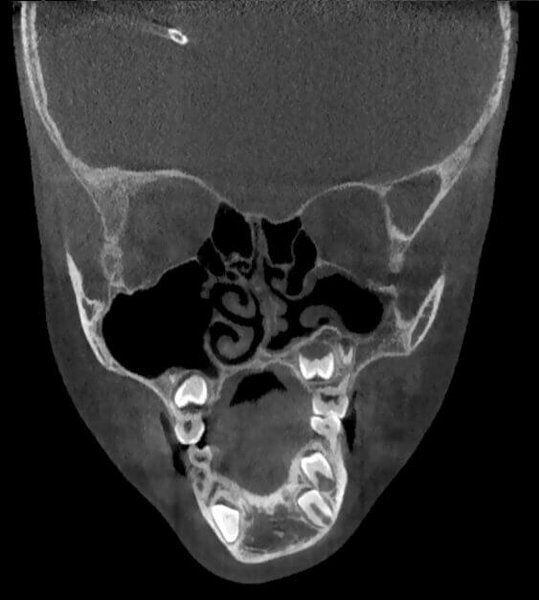

Rottura del pavimento del Seno Mascellare sinistro con Sinusite